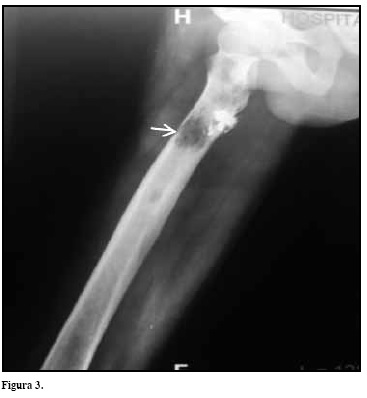

Paciente masculino de 51 años de edad con antecedente de fractura patológica de húmero derecho hace seis meses, asociado a lesiones líticas que durante su investigación fue diagnosticado con mieloma múltiple mediante electroforesis de proteínas, aspirado y biopsia de médula ósea. Fue iniciado tratamiento quimioterapéutico con tal idomida y dexametasona presentado deterioro progresivo de la función renal por lo cuales remitido al Hospital Universitário Gaffrée e Guinle para valoración por nefrología. Al examen de ingreso paciente en regular estado general, palidez muco cutánea generalizada, disnea de medianos esfuerzos, doloróseo, astenia y adinamia. Signos vitales: PA: 100/60 mmHg, FC: 102 lpm,FR: 28 rpm. Fueron solicitados paraclínicos evidenciando anemianormocítica normocrómica, calcio sérico normal, insuficiencia renal(creatinina 3.88 mg/dL-Úrea 93 mg/dL) manejada por nefrología contratamiento conservador; VSG 110 mm/h; radiografía de cráneo, pelvis y fémur derecho evidenciando lesiones osteolíticas (Figuras 1-3).Durante su evolución cursó con síndrome de lisis tumoral tratado con hidratación venosa, alopurinol y alcalinización de la orina con mejoría del cuadro. Presentó hemoglobina de 6 g/dL y hematocrito 18%, se descarta sangrado activo y hemolisis, fueron transfundidos dos unidades de glóbulos rojos con mejoría de los parámetros hematológicos. Valorado por hematología quien instaura tratamiento con esquema CYBORD (ciclofosfamida-bortezomib-dexametasona) por cuatro ciclos con evolución satisfactoria. El paciente recibe alta médica asintomático, con función renal normal (creatinina 1.2 mg/dL-Úrea 23 mg/dL) y continúa en acompañamiento con hematología y nefrología.